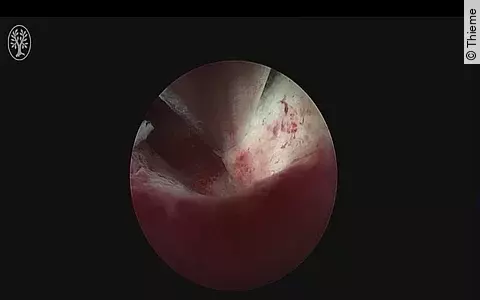

- Hysteroskopie

- Laparoskopie

- Septumdissektion

- Synechiolyse